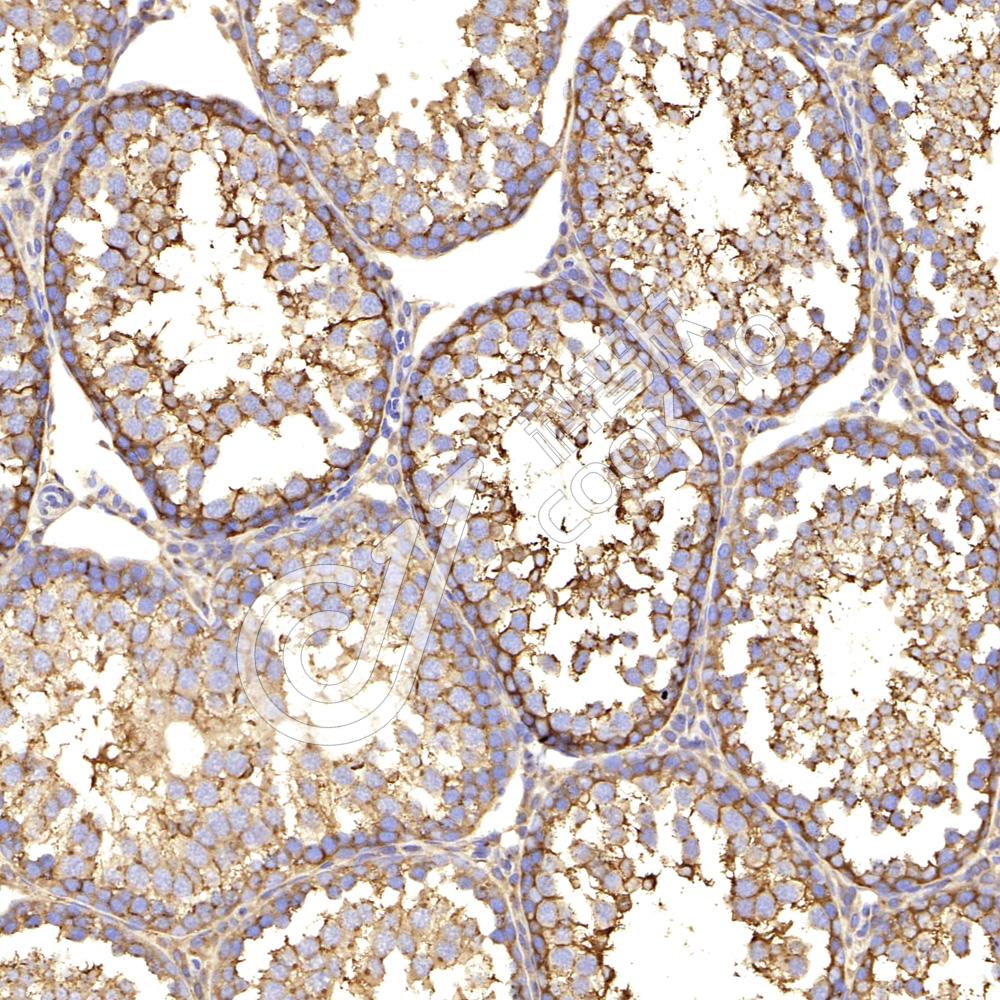

IHC检测IKK alpha蛋白(货号 K133876-2).

样品: 小鼠睾丸, 4%多聚甲醛 (货号KSG1101) 固定12-24小时.

抗原修复: 柠檬酸抗原修复液(干粉, pH 6.0) (KSG1201), 98℃, 20分钟.

—抗: 1: 600稀释, 4℃ 孵育过夜.

二抗: S-vision免疫组化多聚二抗(山羊抗兔),即用型 (货号KB3906), 室温孵育20分钟.